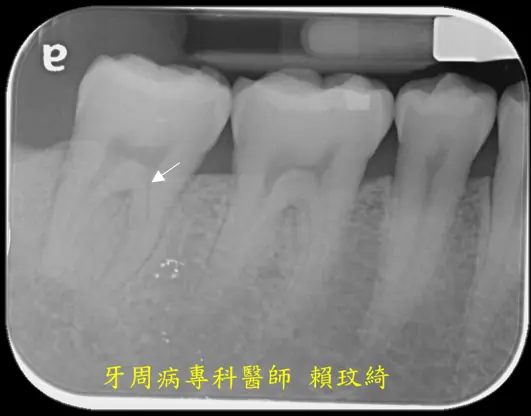

牙周再生手術+牙根覆蓋術

治療前

治療後